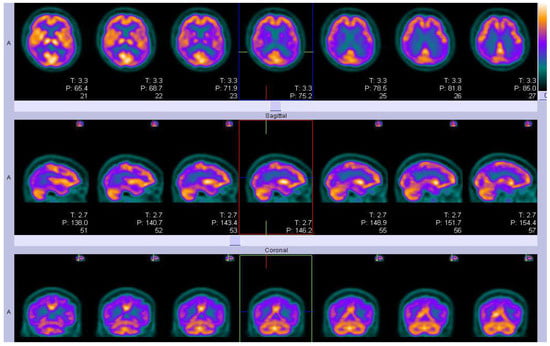

For more than a decade, a characteristic atrophy pattern on 3DT1weighted MRI has been used to distinguish AD from other causes of dementia [137] (Figure 6 and Figure 7). MRI is not only used for visual- and voxel-wise analysis of atrophy pattern to predict different causes of dementia from AD [138], but also the location of WMHs in deep and periventricular brain regions is characteristic of cerebral small vessel disease (CSVD), secondary to hypertension. Microbleeds in cortical area are characteristic of Aβ pathology [139] and also of amyloid-related imaging abnormalities seen as a complication of anti-amyloid therapy.

Figure 6.

Illustrations of MRI biomarkers in AD showing hippocampal volume (green and golden) in participants from the Aberdeen Birth Cohort 1936 study, illustrating hippocampal volume measurement (top row: left and centre; bottom row: left and centre), and white matter hyperintensities (top row: right, bottom row: right) in white and red. (Courtesy—Alison D. Murray, University of Aberdeen).

Figure 7.

Illustrations to show co-existing WMHs on MRI in people with AD. The WMH are seen as white areas around the ventricles (Courtesy—Jennifer Waymont, University of Aberdeen).